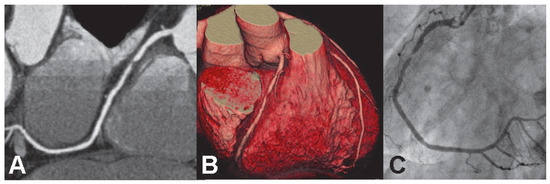

Non-invasive cardiac imaging with magnetic resonance (CMR) and multi-detector computed tomography (MDCT) has progressed rapidly within the past few years and will most likely become and integral part of the diagnostic work-up of patients with known or suspected coronary artery disease (CAD). In [...] Read more.

Non-invasive cardiac imaging with magnetic resonance (CMR) and multi-detector computed tomography (MDCT) has progressed rapidly within the past few years and will most likely become and integral part of the diagnostic work-up of patients with known or suspected coronary artery disease (CAD). In this article, the capabilities, advantages and disadvantages of CMR and MDCT-coronary angiography will be presented and the rationale for their utilisation will be discussed. Therefore, the requirements for a modern management of patients with CAD will be first analysed. Invasive coronary angiography studies in the pre-interventional area showed, that CAD progresses through repeated ruptures of vulnerable plaques. Current imaging techniques are not developed enough for a reliable characterisation of vulnerable plaques in the coronary system. However, vulnerable plaques are defined not only by composition, but also by their stenosis severity, since high-grade stenosis are associated with an increased risk of rupture and occlusion. These severe, haemodynamically significant coronary lesions can be detected by CMR perfusion imaging or by anatomical depiction by MDCT-coronary angiography. In large CMR perfusion multicenter trials, the sensitivity and specificity for detection of ≥50% diameter stenoses by CMR perfusion imaging ranges from 86–91% and 65–84%, respectively. In “MR-IMPACT”, the MR perfusion technique was superior to single photon-emission computed tomography (91% and 67% with CMR versus 74% and 57% with SPECT) with exclusion rates of 2.2% and 3.6%, respectively. Advantages of CMR are: high diagnostic performance as proven in multicenter trials, no harmful radiation exposure, and thus repeatability, and the CMR examination is safe and lasts 1–1.5 hours only. For MDCT-coronary angiography, one multicenter trial is available and reported an exclusion rate of 42% of patients because of inadequate image quality, and thus, could not confirm the single center studies. In single center studies sensitivities and specificities range from 82–95% and 86–98%, respectively. MDCT coronary angiography is relatively easy to apply and lasts about 15 minutes. Due to the radiation exposure, MDCT-coronary angiography seems not ideal for monitoring CAD. In current practice, patients are examined only after symptoms occur (re-active strategy). With this re-active strategy, about every second cardiac death occurs before the patient reaches the hospital or the catheter-lab for invasive treatment (statistics USA 2004). The goal of an active strategy is therefore to detect high-risk patients earlier by modern diagnostic techniques and to perform revascularisations in these patients before potentially deadly infarcts occur. Since CAD is a chronic disease, an active strategy would involve a repeated risk stratification. For such an active strategy, an ideal test should therefore be highly accurate, non-harmful, and thus, repeatable, and unexpensive. Full article

Figure 1